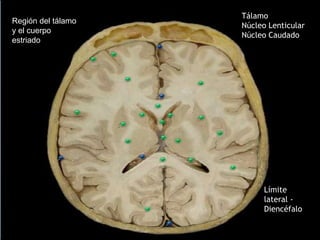

Región del tálamo

y el cuerpo

estriado

Límite

lateral -

Diencéfalo

Tálamo

Núcleo Lenticular

Núcleo Caudado

BRAZO ANTERIOR:

Delimitado por el núcleo

lenticular y la cabeza del

núcleo caudado.

RODILLA (GENU):

Se localiza en posición medial

respecto del ápice del núcleo

lenticular.

BRAZO POSTERIOR:

Entre el núcleo lenticular y el

tálamo.

*Porción retrolenticular:

Región situada detrás del

núcleo lenticular.

*Porción sublenticular:

Formada por fibras que

pasan por debajo de la

parte posterior del núcleo